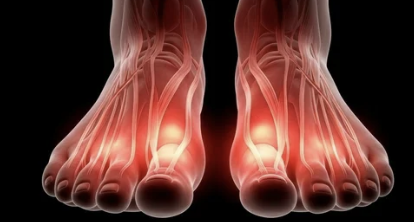

3️⃣ 무지외반증(엄지발가락 변형)

- 엄지발가락이 휘면서 발바닥 압력이 특정 부위에 집중

- 발바닥 앞쪽(중족골 부위)에 굳은살·통증 동반

- 원인: 하이힐·폭 좁은 신발, 유전적 요인